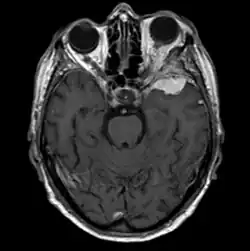

Sphenoid wing meningioma in magnetic resonance imaging (T1w contrast enhanced)

Sphenoid wing meningiomas are diagnosed by the combination of suggestive symptoms from the history and physical and neuroimaging by magnetic resonance imaging (MRI) or computer averaged tomography (CT). Tumors growing in the inner wing (clinoidal) most often cause direct damage to the optic nerve leading especially to a decrease in visual acuity, progressive loss of color vision, defects in the field of vision (especially cecocentral), and an afferent pupillary defect. If the tumor continues to grow and push on the optic nerve, all vision will be lost in that eye as the nerve atrophies. Proptosis, or anterior displacement of the eye, and palpebral swelling may also occur when the tumor impinges on the cavernous sinus by blocking venous return and leading to congestion. Damage to cranial nerves in the cavernous sinus leads to diplopia. Cranial nerve VI is often the first affected, leading to diplopia with lateral gaze. If cranial nerve V-1 is damaged, the patient will have pain and altered sensation over the front and top of the head. Horner's syndrome may occur if nearby sympathetic fibers are involved.

Tumors found in the external third of the sphenoid are of two types: en-plaque and globoid meningiomas. En plaque meningiomas characteristically lead to slowly increasing proptosis with the eye angled downward. Much of this is due to reactive orbital hyperostosis. With invasion of the tumor into the orbit, diplopia is common. Patients with globoid meningiomas often present only with signs of increased intracranial pressure. This leads to various other symptoms including headache and a swollen optic disc. The differential diagnosis for sphenoid wing meningioma includes other types of tumors such as optic nerve sheath meningioma, cranial osteosarcoma, metastases, and also sarcoidosis. Following the physical exam, the diagnosis is confirmed with neuro-imaging. Either a head CT or MRI with contrast such as gadolinium is useful, as meningiomas often show homogenous enhancement. Angiography looking for signs like stretched arteries may be used to supplement evaluation of vascular involvement and to determine whether embolization would be helpful if surgery is being considered.